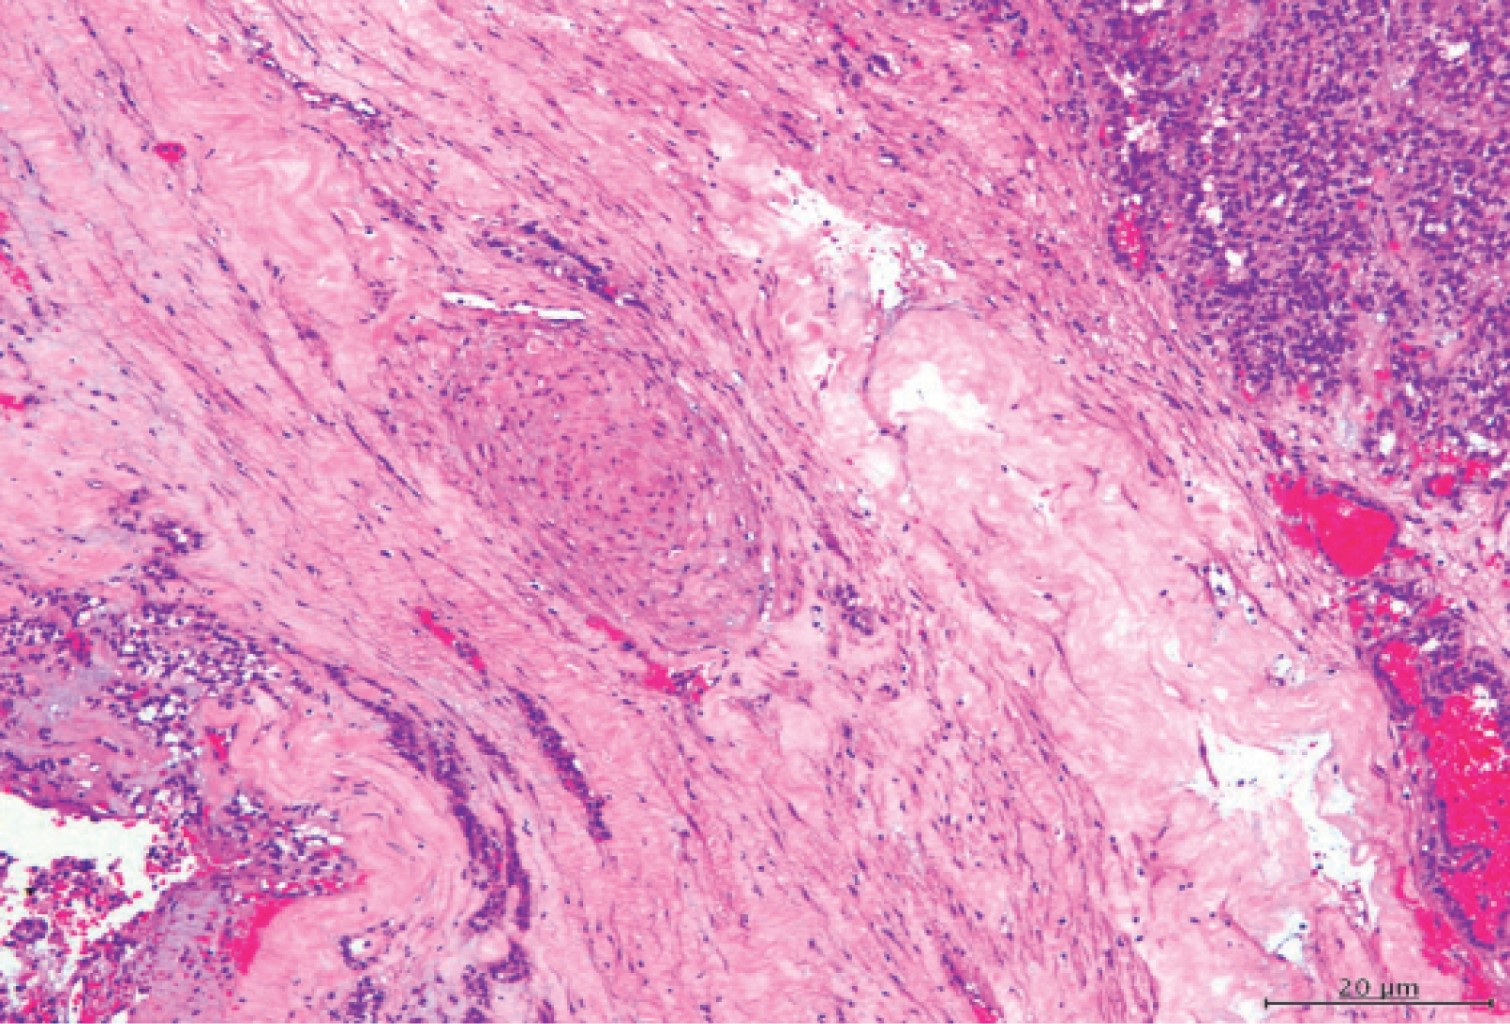

The histopathological study revealed findings of a pancreatic solid papillary carcinoma with absence of malignancy in surrounding tissues such as greater omentum and pancreatic lymph node (Figure 6).

Microscopically there are uniform cells of epithelioid appearance, rounded or oval, with central nucleus and fine chromatin without mitotic activity. The stroma is finely vascularized and cholesterol crystals, histiocytes and calcifications are usually seen.4,5,7 The report of the microscopic study supported the diagnosis of a papillary solid carcinoma with presence of vascular embolisms, perineural involvement, presence of scattered calcifications and degenerative cystic changes that also required immunohistochemical technique to corroborate the diagnosis.